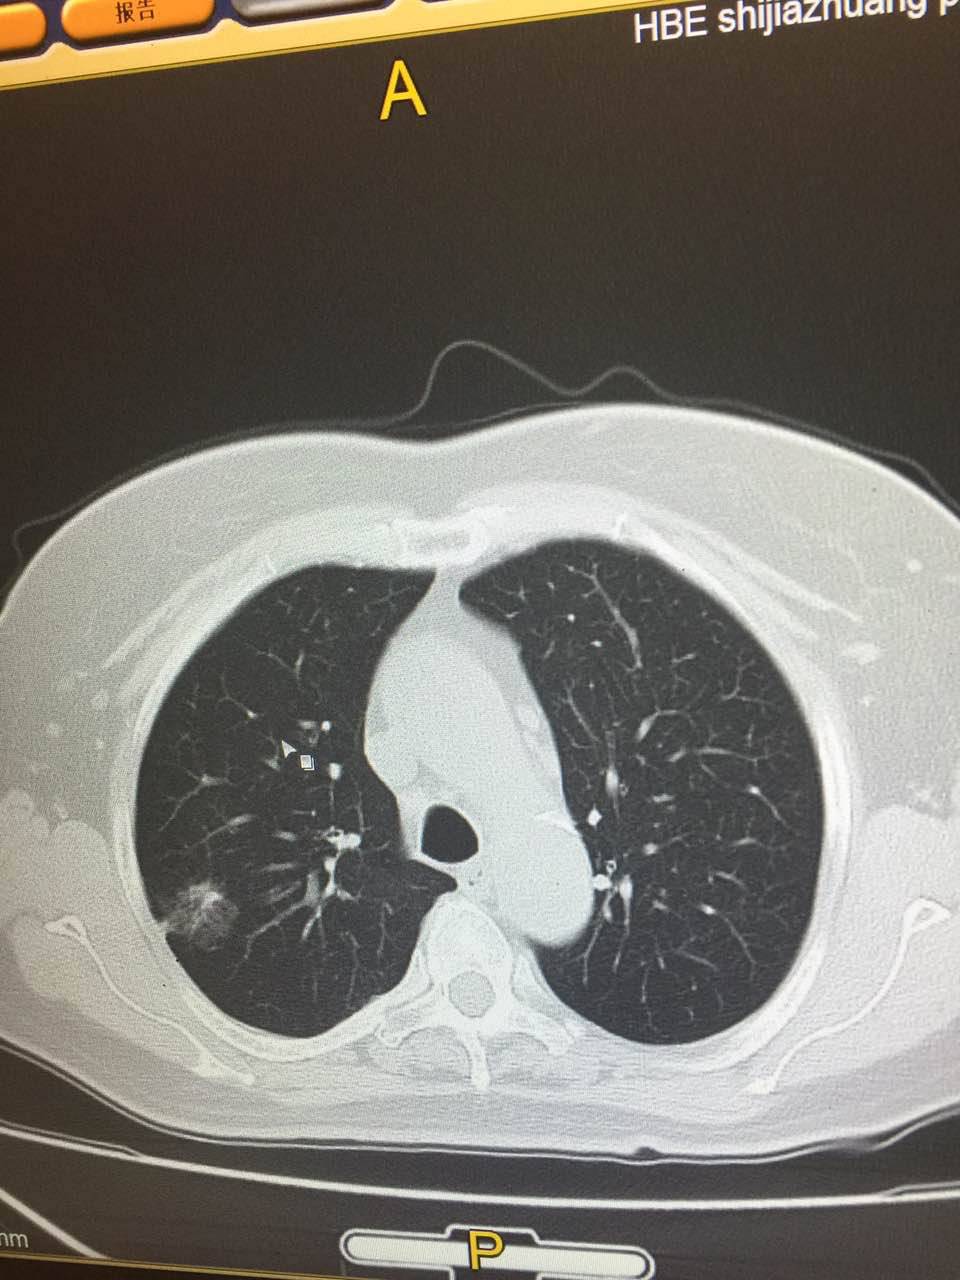

陈医生,这是我母亲的CT,您看一下手机

@陈医生,这是我母亲的CT,花开未全月半弯的CT直接就确诊了吗?

很好,做的很好,看到了